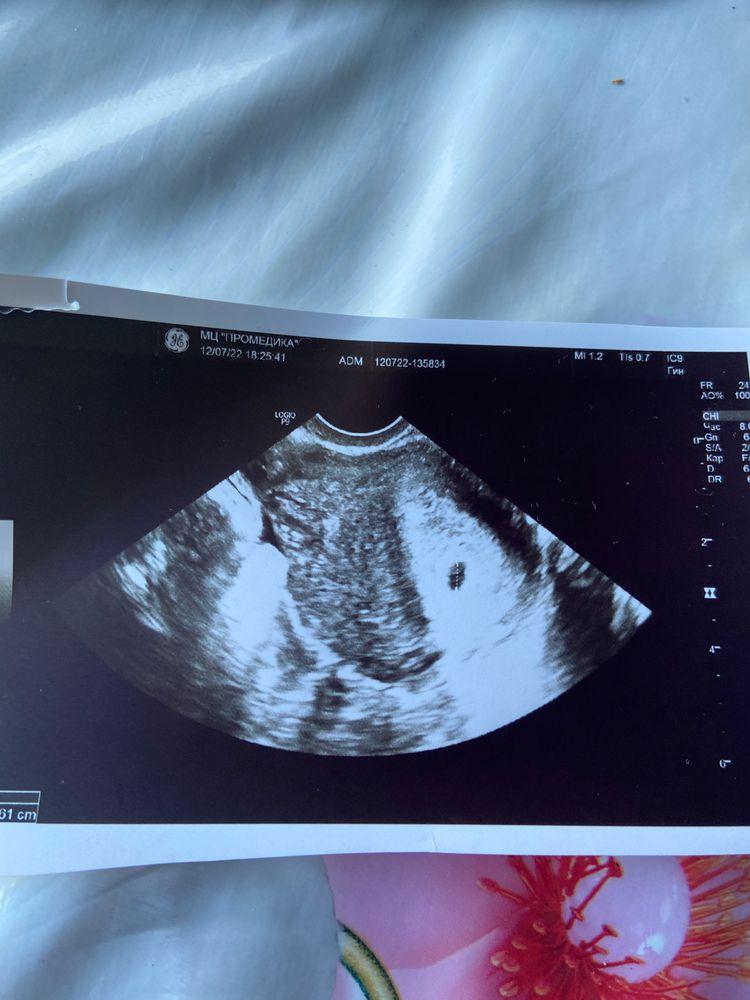

Узи на 5+1 акушерской неделе

Все таки пошла сегодня на узи, хоть все говорили,что ещё очень рано.Плодное яйцо уже видно,оно в матке,внутри пока конечно ещё ничего не видно,но я хотя бы исключила для себя внематочную..

Срок по узи 3-4 недели,теперь через две недели идти,чтобы увидеть эмбрион и возможно уже услышать сердечко.

Единственное врач сказал есть тонус матки,потому что яичко чуть вытянутой формы,назначила пить ношпу или магний б6

Вы увидите просто малюсенькое яичко,у меня 6мм оно)